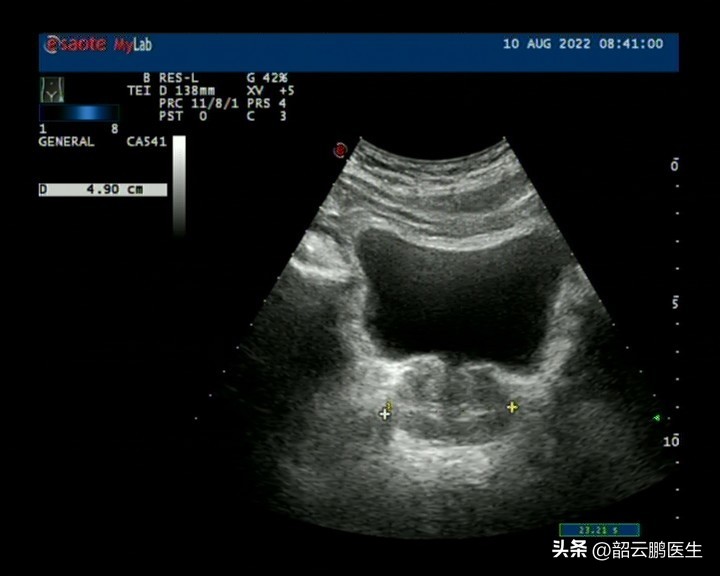

病例一:前列腺增生

前列腺增生是最常見的引起中老年男性排尿障礙的疾病,也是很多老年人最熟知的問題。病例一的臨床表現非常典型,彩超結果提示前列腺體積4.9*3.1*3.8cm,殘余尿20ml。從彩超這個結果我們不難看出,雖然前列腺體積有所增大,但是相較于正常4*3*2cm前列腺體積增加有限。這時我們考慮到了一個問題,叫做“小體積前列腺增生”。

這種類型的前列腺增生以阻塞尿道為主,會較早地引起患者的排尿問題。為了證實這個診斷,我們進行了膀胱鏡檢查,可以看到前列腺左右側葉向尿道擠壓,出現了尿道梗阻的表現。在進行了前列腺電切以后,患者的排尿癥狀明顯改善了。